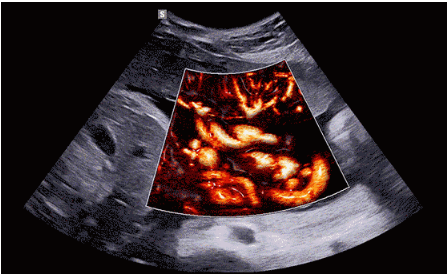

CrystalLive?是三星最新的超聲成像引擎,同時(shí)增強(qiáng)了2D圖像處理能力、3D渲染能力和彩色信號處理能力,能夠在復(fù)雜情況下提供出色的圖像性能,具備檢測外周血管、微循環(huán)血流的能力。

3D/4D成像方面,Hera i 10通過結(jié)合先進(jìn)的圖像渲染技術(shù),著重加強(qiáng)了邊緣和小結(jié)構(gòu)的可視化能力。